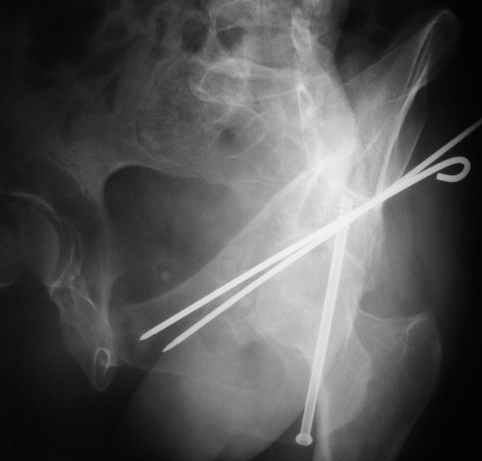

Женя! Класный перелом. Отлично репонируется изнутри таза, но лучше фиксированть сзади. Классический перелом для двустороннего доступа.

Однако есть альтернатива. Репозиция из подвздошного доступа тазовыми щипцами с разнодлинными браншами или тазовым пистолетом, а фиксация задней колонны через седалищный бугор или тазрвыми винтами 4,5 или каннюлированными 6,5 или 7,3. По-моему я посылал на ортофорум такой снимок, когда жаловался на ишемический неврит седалищного нерва через сутки после операции. Не забудь про шейку бедра - мне кажется будет хорош длинный PFN любой фирмы, какую ты найдешь, а нет так UFN + miss a nail, как это здорово делают мои земляки - Ебурбуки. Пока.

10.02.04